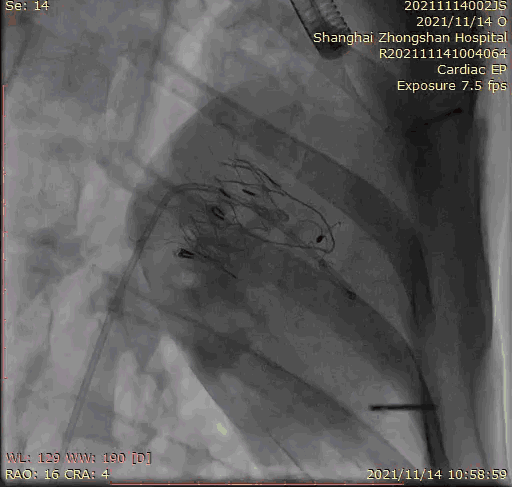

2021年11月14日星期日,復(fù)旦大學(xué)附屬中山醫(yī)院(以下簡稱中山醫(yī)院)葛均波院士團(tuán)隊(duì)成功應(yīng)用經(jīng)血管介入三尖瓣置換產(chǎn)品Lux-Valve Plus完成臨床前研究,并獲得圓滿成功!此次研究的成功預(yù)示經(jīng)血管三尖瓣產(chǎn)品Lux-Valve Plus已完成臨床前準(zhǔn)備,即將開啟后期的正式臨床研究!

上海中山醫(yī)院葛均波院士、錢菊英院長、周達(dá)新教授、潘文志教授、潘翠珍教授、李偉教授共同完成此次臨床前研究。術(shù)后葛均波院士對Lux-Valve Plus的器械操作性能給予了高度評價(jià),DSA和超聲影像也顯示出在本次研究中Lux-Valve Plus的安全性和有效性俱佳。

本次臨床前研究經(jīng)右側(cè)頸靜脈置入LuX-Valve Plus輸送系統(tǒng)可調(diào)彎鞘管,在DSA及超聲引導(dǎo)下將人工三尖瓣瓣膜植入到原有三尖瓣位置,利用獨(dú)特的錨定技術(shù)將人工瓣膜支架可靠固定在預(yù)定的位置。